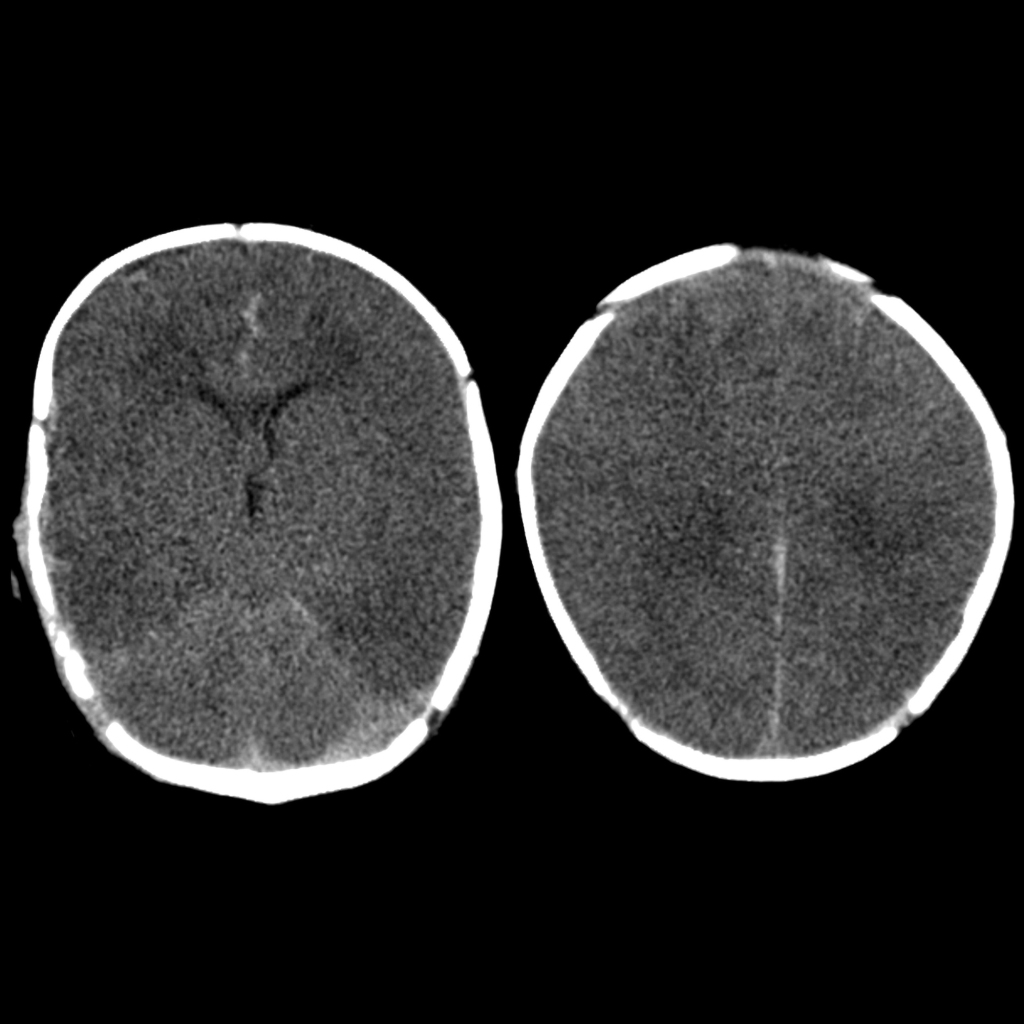

A 10-month-old infant is brought to the emergency by his parents after a seizure. The parents report no history of trauma, fever, or a family history of seizures. However, they both say that the patient fell while he was running. Neurologic examination was normal. A head CT scan was ordered and is shown in figure A. Which of the following is most likely found in this patient?